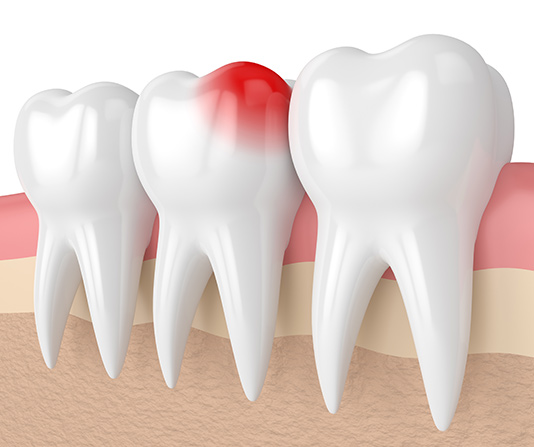

A toothache is bad on its own, but what happens when it suddenly disappears? This can be a sign that your tooth has died and may need extraction. At Nu Dentistry Spring, our dentists always do our best to keep our patients’ smiles bright, healthy, and whole. However, when you need tooth removal, our skilled team makes the entire process quick and painless. Whether you need extraction due to cavities, gum disease, broken teeth, or impactions, you have nothing to worry about with our expert dentists in charge. Even in a dental emergency, you can count on our amazing team to make your tooth extraction procedure a breeze. As soon as you walk through our front doors, we don’t waste a moment to have your smile looked at. We will perform a thorough examination to ensure tooth extraction is your best option before quickly creating a winning plan to take care of your tricky tooth. And with both local anesthetic and dental sedation options available, you won’t feel a thing during your time in the dental chair. Need emergency tooth removal? Contact our dental office right now at (713) 489-0538 to book an urgent appointment.